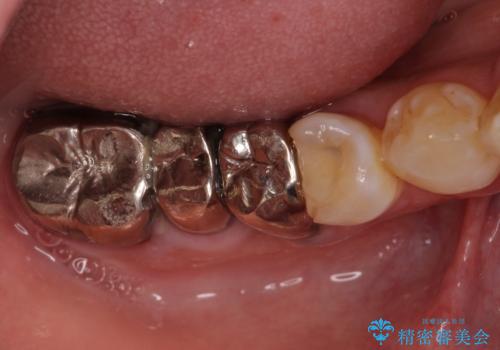

左上の奥歯は2本抜歯が必要であったため、治療期間中は右側に負担がかかり、頻繁に仮歯が壊れてしまいました。

左上に仮歯が装着されたからは咬み合わせが安定し、スムーズに治療を進めることができました。